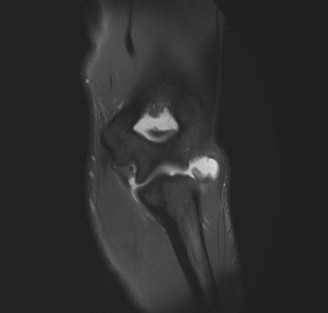

Imaging should include x-rays, which may demonstrate posterior glenoid bone loss or an impaction fracture on the anterior-superior humeral head (Fig. 2–38). CT images with 3D reconstructions can be very useful when assessing the extent of glenoid bone loss and evaluating glenoid and humeral version. Normal glenoid version is from −2 to −8 degrees of retroversion, and this may be increased in posterior instability. MRI can also be useful when assessing the posterior labrum (Fig. 2–39).

Figure 2–38 Radiographs showing a posterior shoulder dislocation.

Figure 2–39 MRI showing a posterior labrum tear.